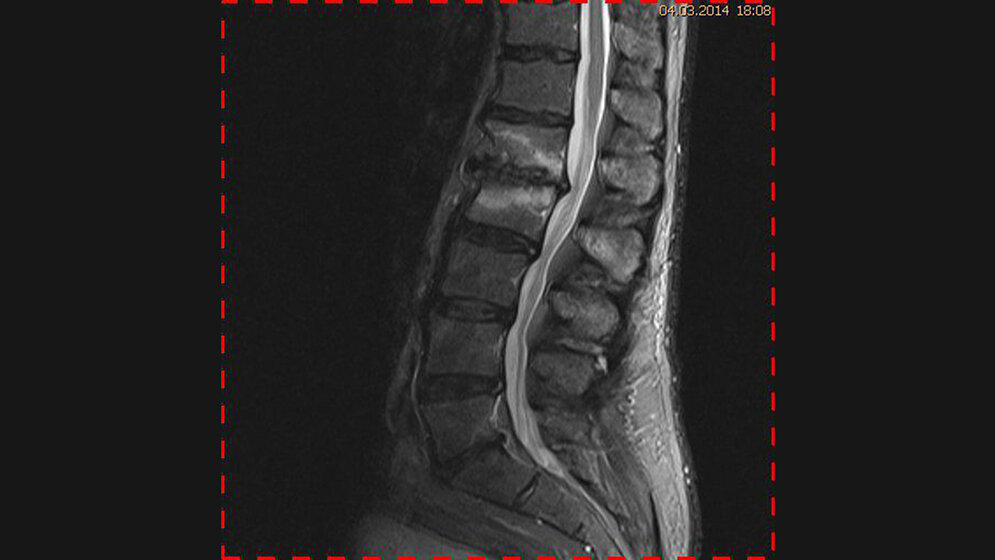

Degenerative Veränderungen: Morbus Baastrup

Schnittbilddiagnostik der Wirbelsäule (1.13)

Die bildgebenden Untersuchungsverfahren der Wirbelsäule werden mit unterschiedlichen Indikationen angefordert. Zum Nachweis des generellen Ausmaßes der degenerativen Veränderungen reichen Röntgenaufnahmen in zwei Ebenen, gelegentlich ergänzt durch Aufnahmen in Funktionsstellungen, aus.

Der Morbus Baastrup kommt mit hoher Frequenz bei älteren Menschen vor und entwickelt sich mit zunehmendem Alter. Die Patienten mit M. Baastrup können Schmerzen, verursacht durch eine Periostreizung, Bursitis zwischen den Processus spinosus oder eine Stress-

fraktur, haben.